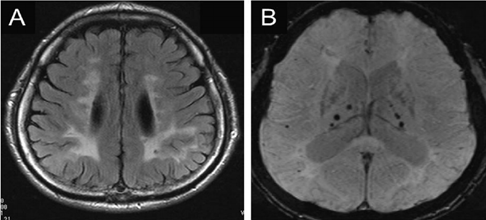

高血壓可導致皮質和皮質下小動脈硬化。通常與深部腦出血和CMBs、基底節EPVS、梗死(尤其是腔隙,易發生在基底節和腦幹)和WMH有關。CMBs傾向於出現在深灰質和腦幹,較少出現在小腦或腦葉(圖2)。

圖2 高血壓患者SWI基底節區多發微出血。

法布里病(Fabry disease)是一種由α-半乳糖苷酶的A基因突變引起的X連鎖溶酶體儲存障礙性疾病,其CMBs無特定的MRI表現,可在幕下(腦幹或小腦)和/或幕上(基底節、丘腦、腦室周圍白質、皮質下區)觀察到(圖5)。

圖5 49歲男性Fabry病患者,FLAIR(A)顯示腦白質高訊號,SWI(B)顯示雙側丘腦多發微出血。